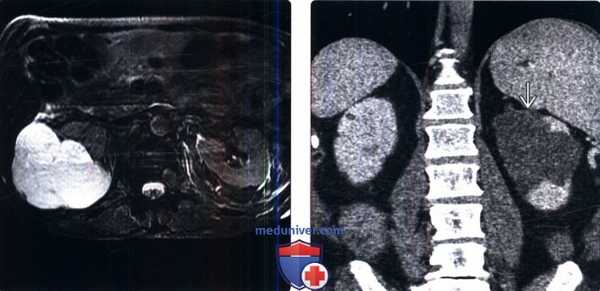

(Слева) КТ без контрастирования, аксиальная проекция: гиперденсная (100 HU) киста ВЗ левой почки (класс 2 по Босняку).

(Справа) КТ с контрастированием, аксиальная проекция: у того же пациента выявлено контрастирование кисты левой почки (106 HU). Гиперденсные кисты почки, имеющие плотность более 70 HU на бесконтрастной КТ, считают доброкачественными. Образования мягкотканной плотности (20-70 HU) на бесконтрастной КТ следует оценивать с помощью УЗИ или с использованием специализированного почечного КТ-протокола для дифференцирования истинных солидных образований от гиперденсных кист.